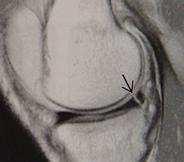

- 무릎관절에 비틀리는 힘이 가해지는 외상 후, 잠김 현상이 발생하거나, 무릎관절이 어긋나는 느낌이 발생하면서 내측 혹은 외측 관절면을 따라 통증이 발생합니다. MRI로 90%이상 정확히 진단할 수 있습니다. 치료는 관절경 검사로 확진 및 이에 대한 수술적 치료를 시행할 수 있습니다.